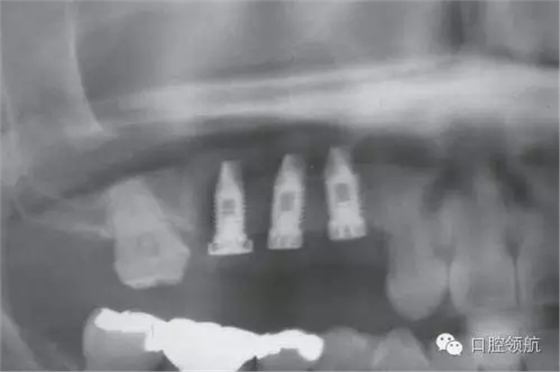

圖4 術后即刻的曲面斷層影像

術后1周準備拆線時,發(fā)現(xiàn)覆蓋螺絲部分露出。遂延期1周拆線,并每2天清洗一次創(chuàng)面,為了在暴露的覆蓋螺絲周圍有正常軟組織環(huán)繞,拆線后每隔2~3天來院,用生理鹽水清潔軟毛牙刷去除軟垢,保持創(chuàng)面清潔穩(wěn)定(圖6~圖10)。

圖6 術后周圍黏膜的變化。術后1個月的口內(nèi)像

圖7 術后周圍黏膜的變化 術后4個月的口內(nèi)像 種植體周圍未見炎癥表現(xiàn)